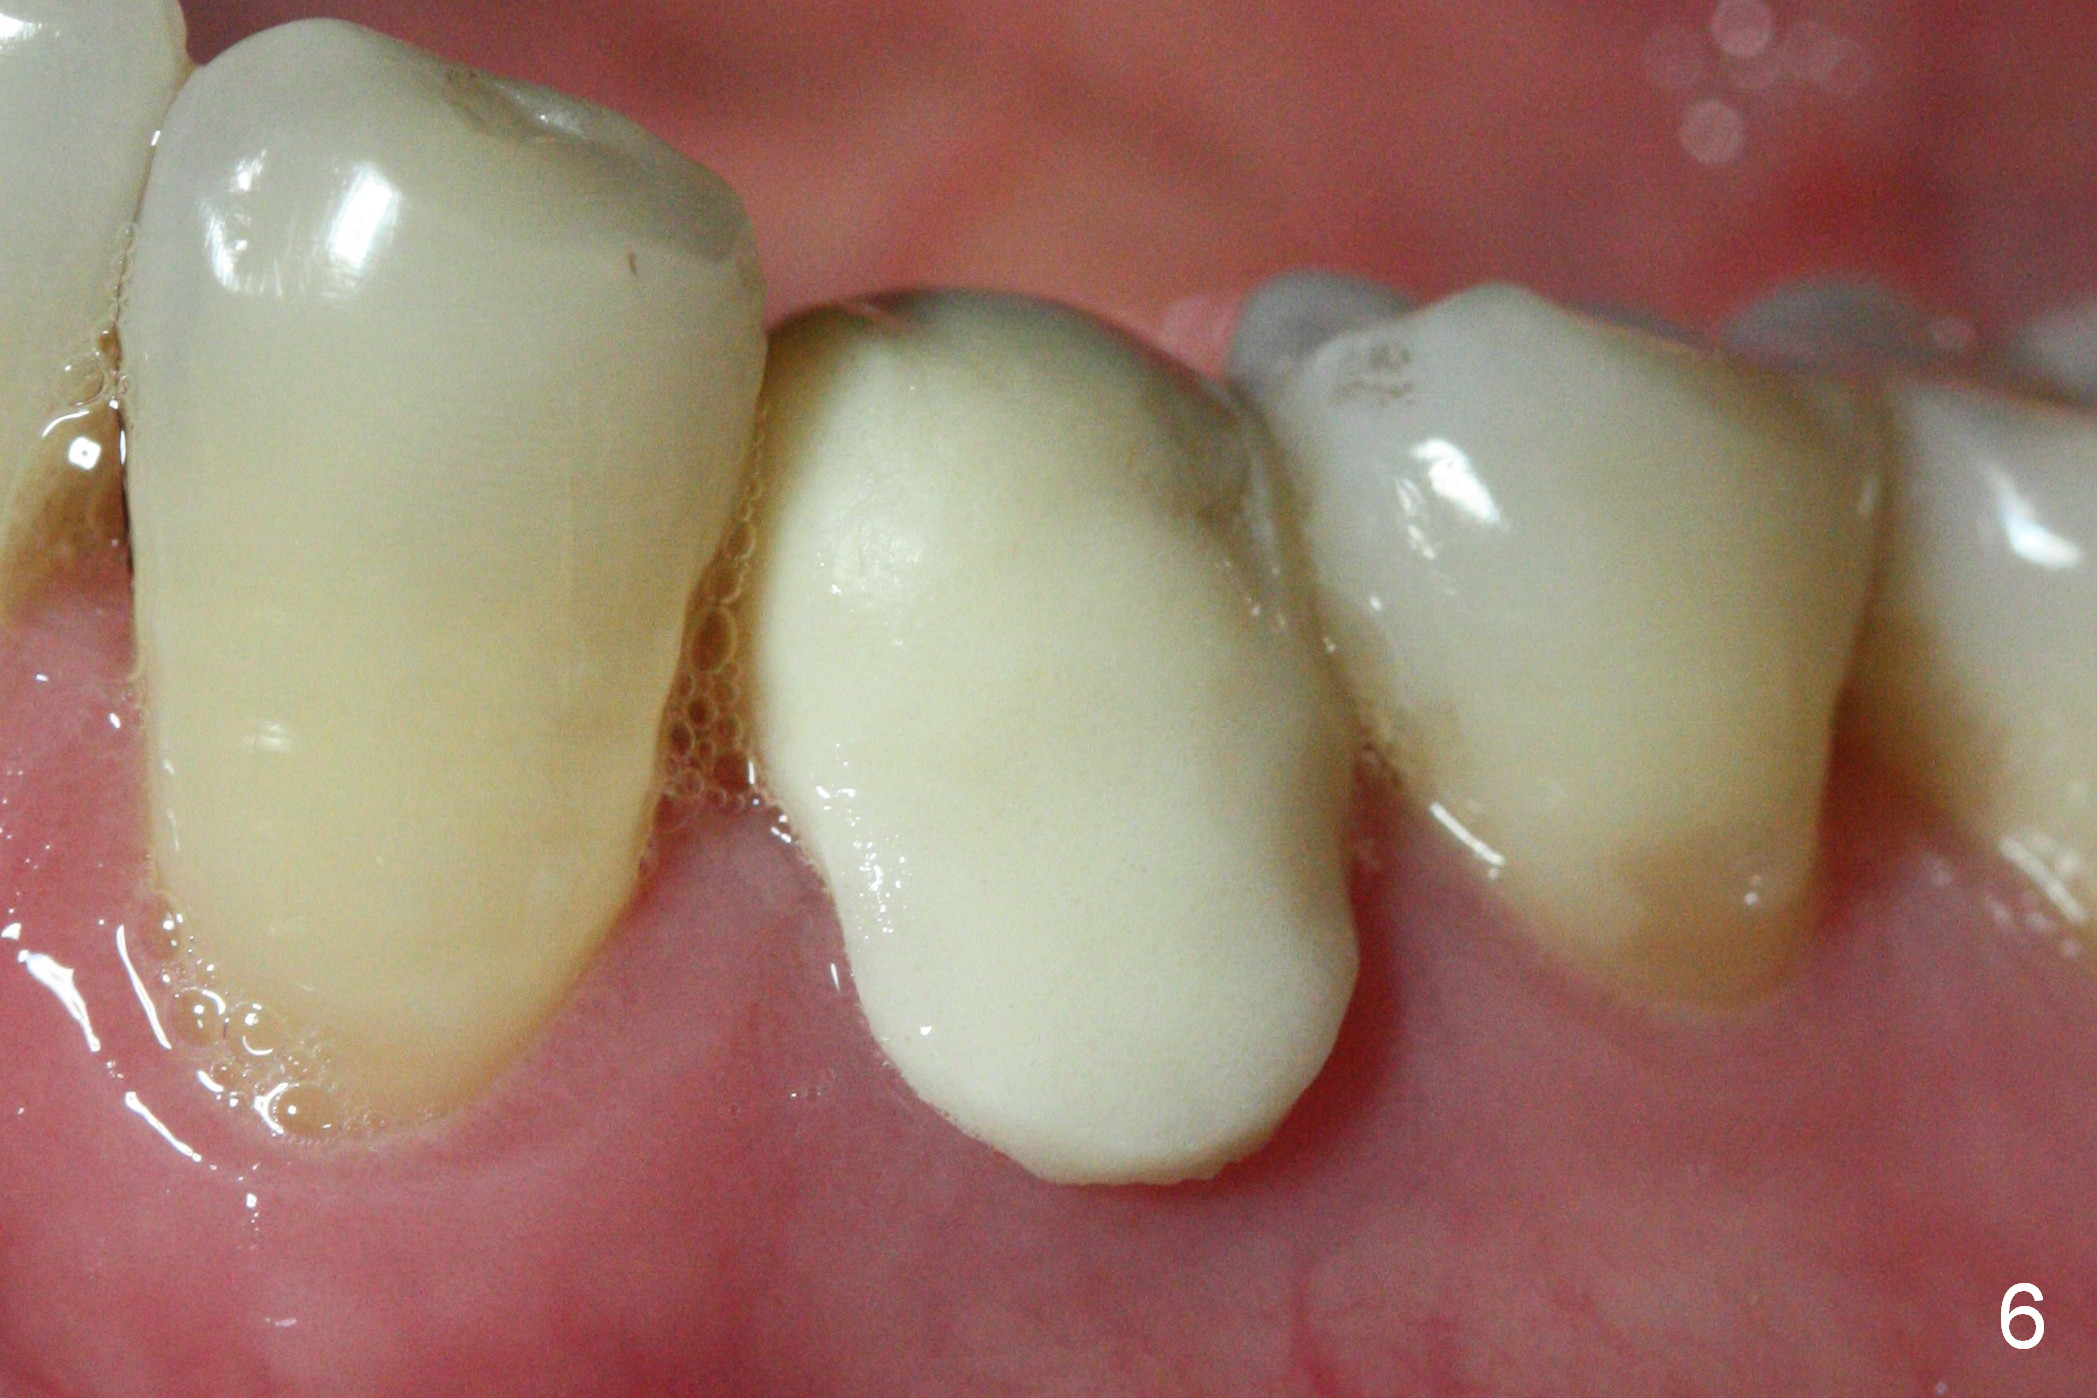

The patient returns for provisional revision 2 weeks postop (Fig.6).  The bone graft remains in place (Fig.7).  The buccal margin of the provisional is reduced (Fig.8).